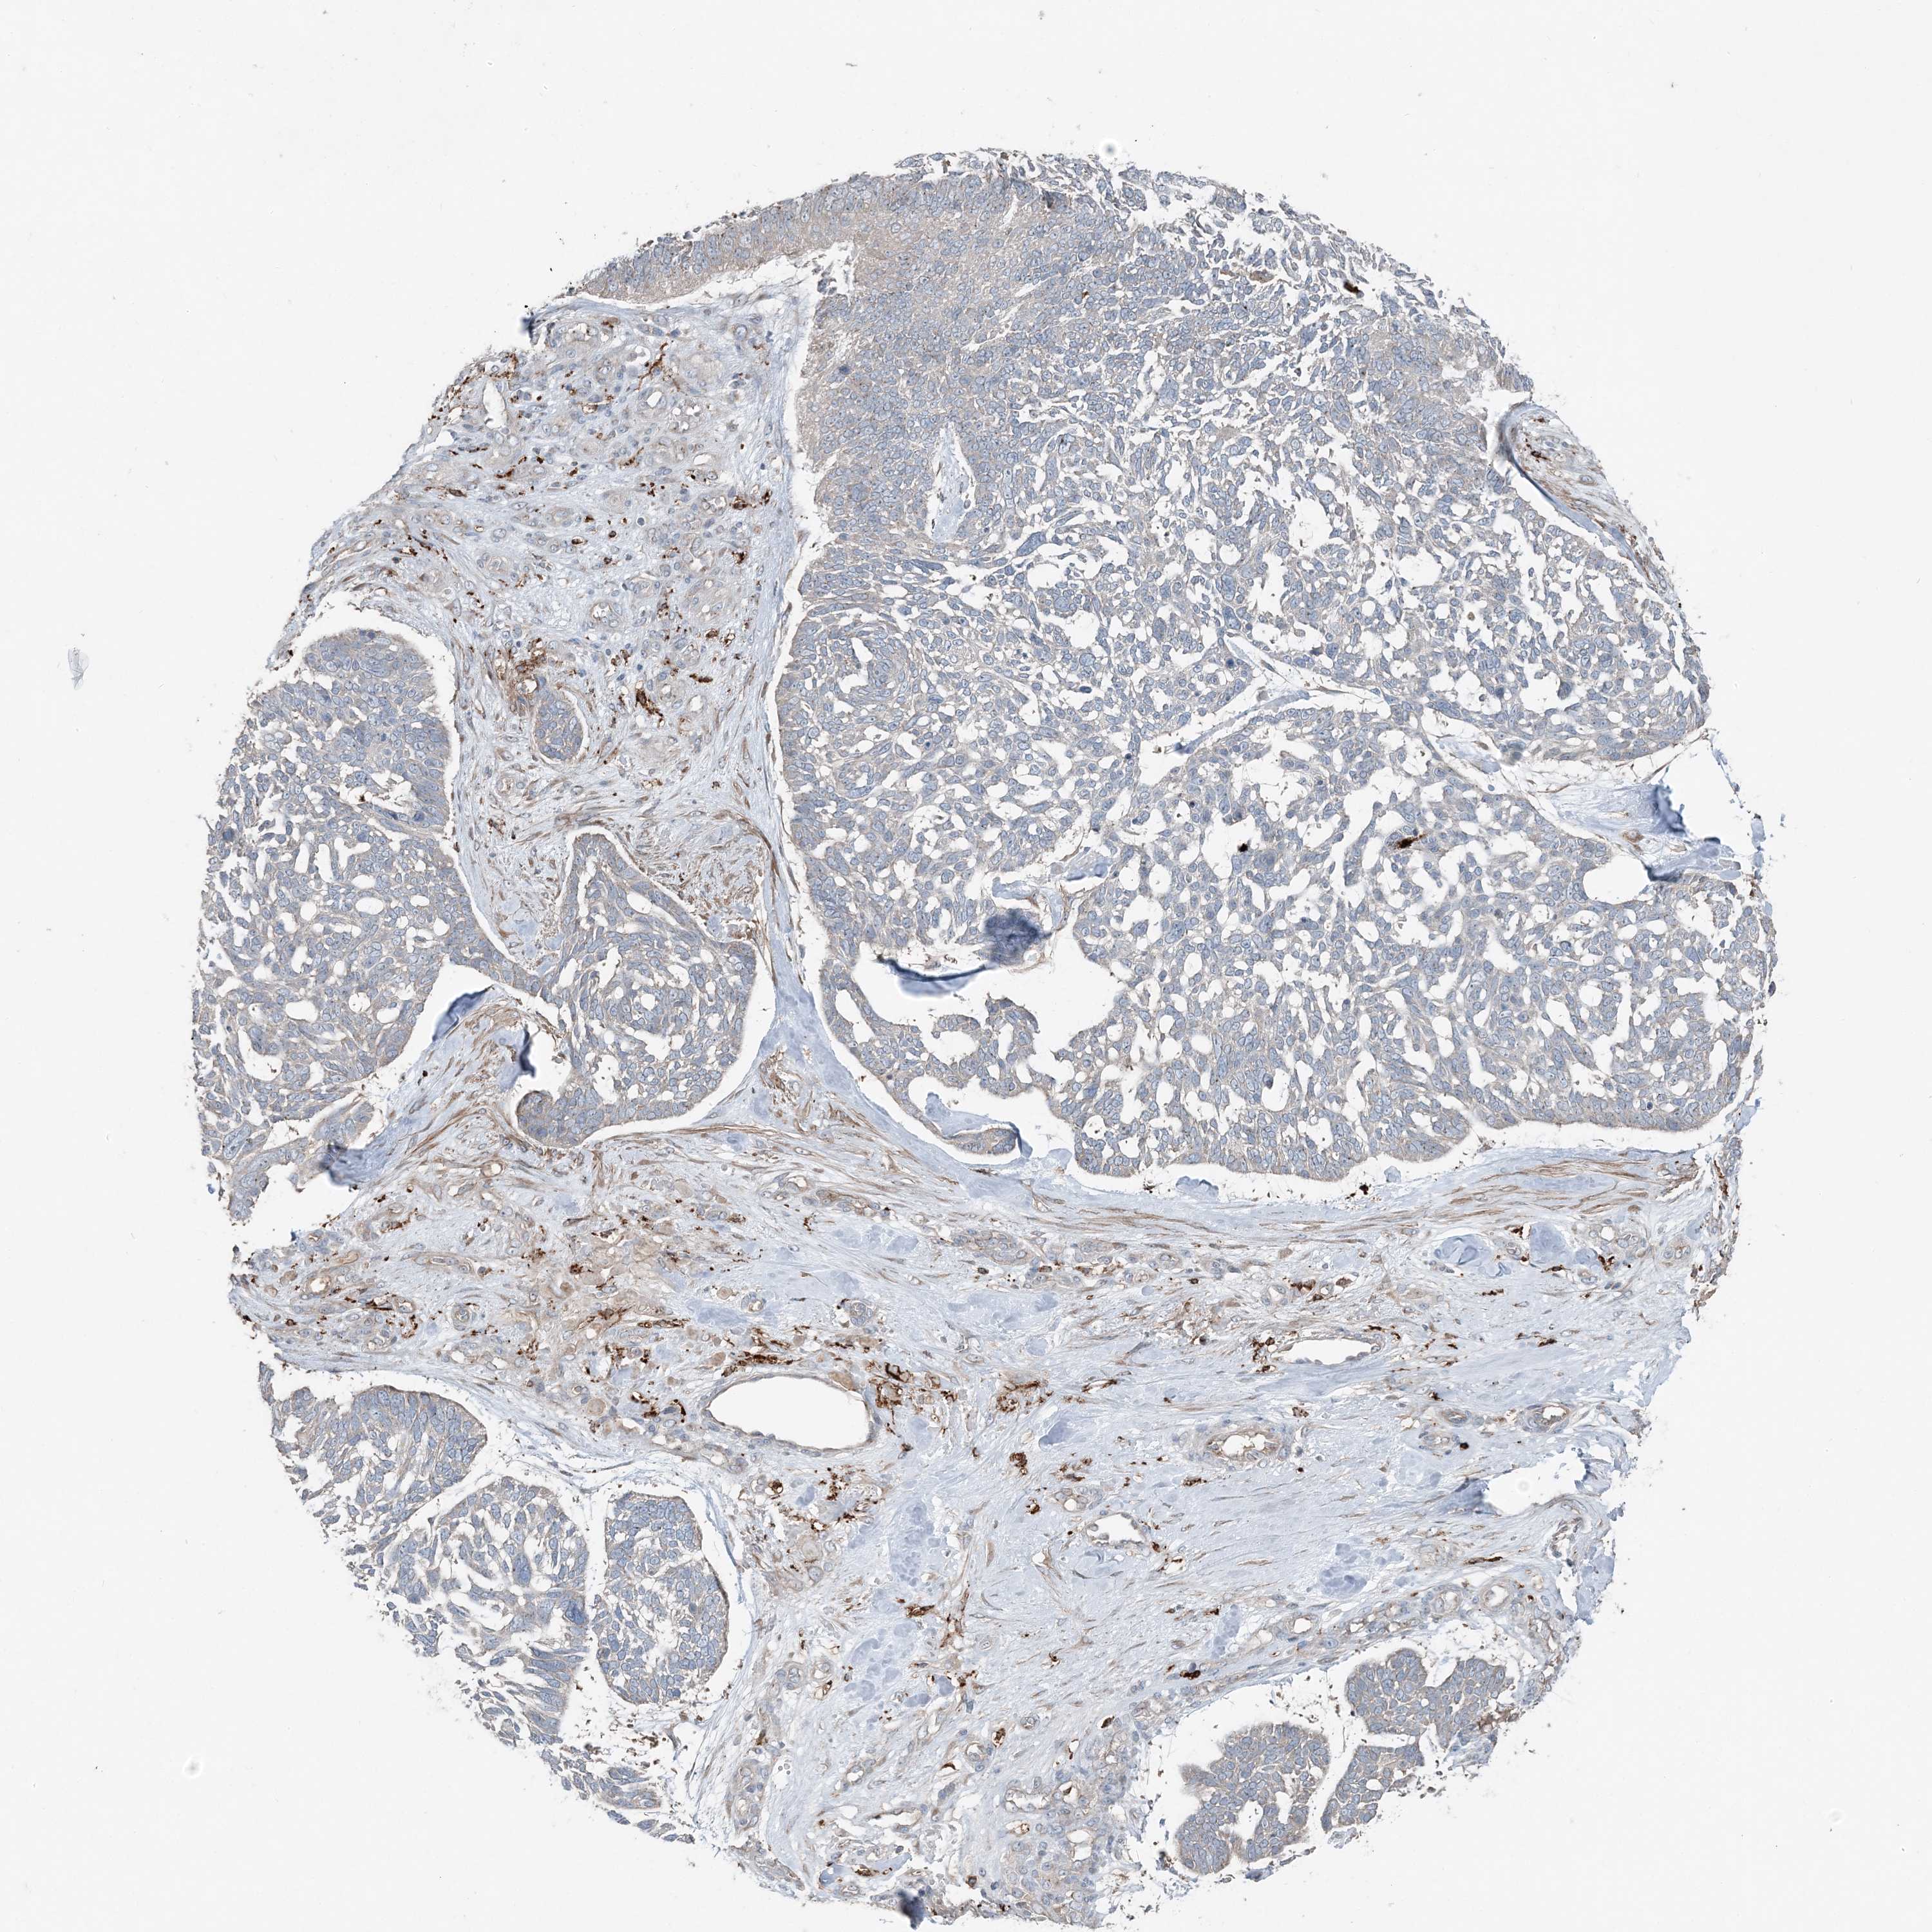

SKIN CANCER - Protein expressioni

A mouse-over function shows sample information and annotation data. Click on an image to view it in a full screen mode. Samples can be filtered based on level of antibody staining by selecting one or several of the following categories: high, medium, low and not detected. The assay and annotation is described here.

Antibody stainingi

Antibody staining in the annotated cell types in the current human tissue is reported as not detected, low, medium, or high, based on conventional immunohistochemistry profiling in selected tissues. This score is based on the combination of the staining intensity and fraction of stained cells.

Each image is clickable and will lead to virtual microscopy that enables deeper exploration of all samples and also displays staining intensity scores, fraction scores and subcellular localization as well as patient and tissue information for each sample.

Antibody HPA036492

Basal cell carcinoma

Squamous cell carcinoma, NOS

Squamous cell carcinoma, metastatic, NOS